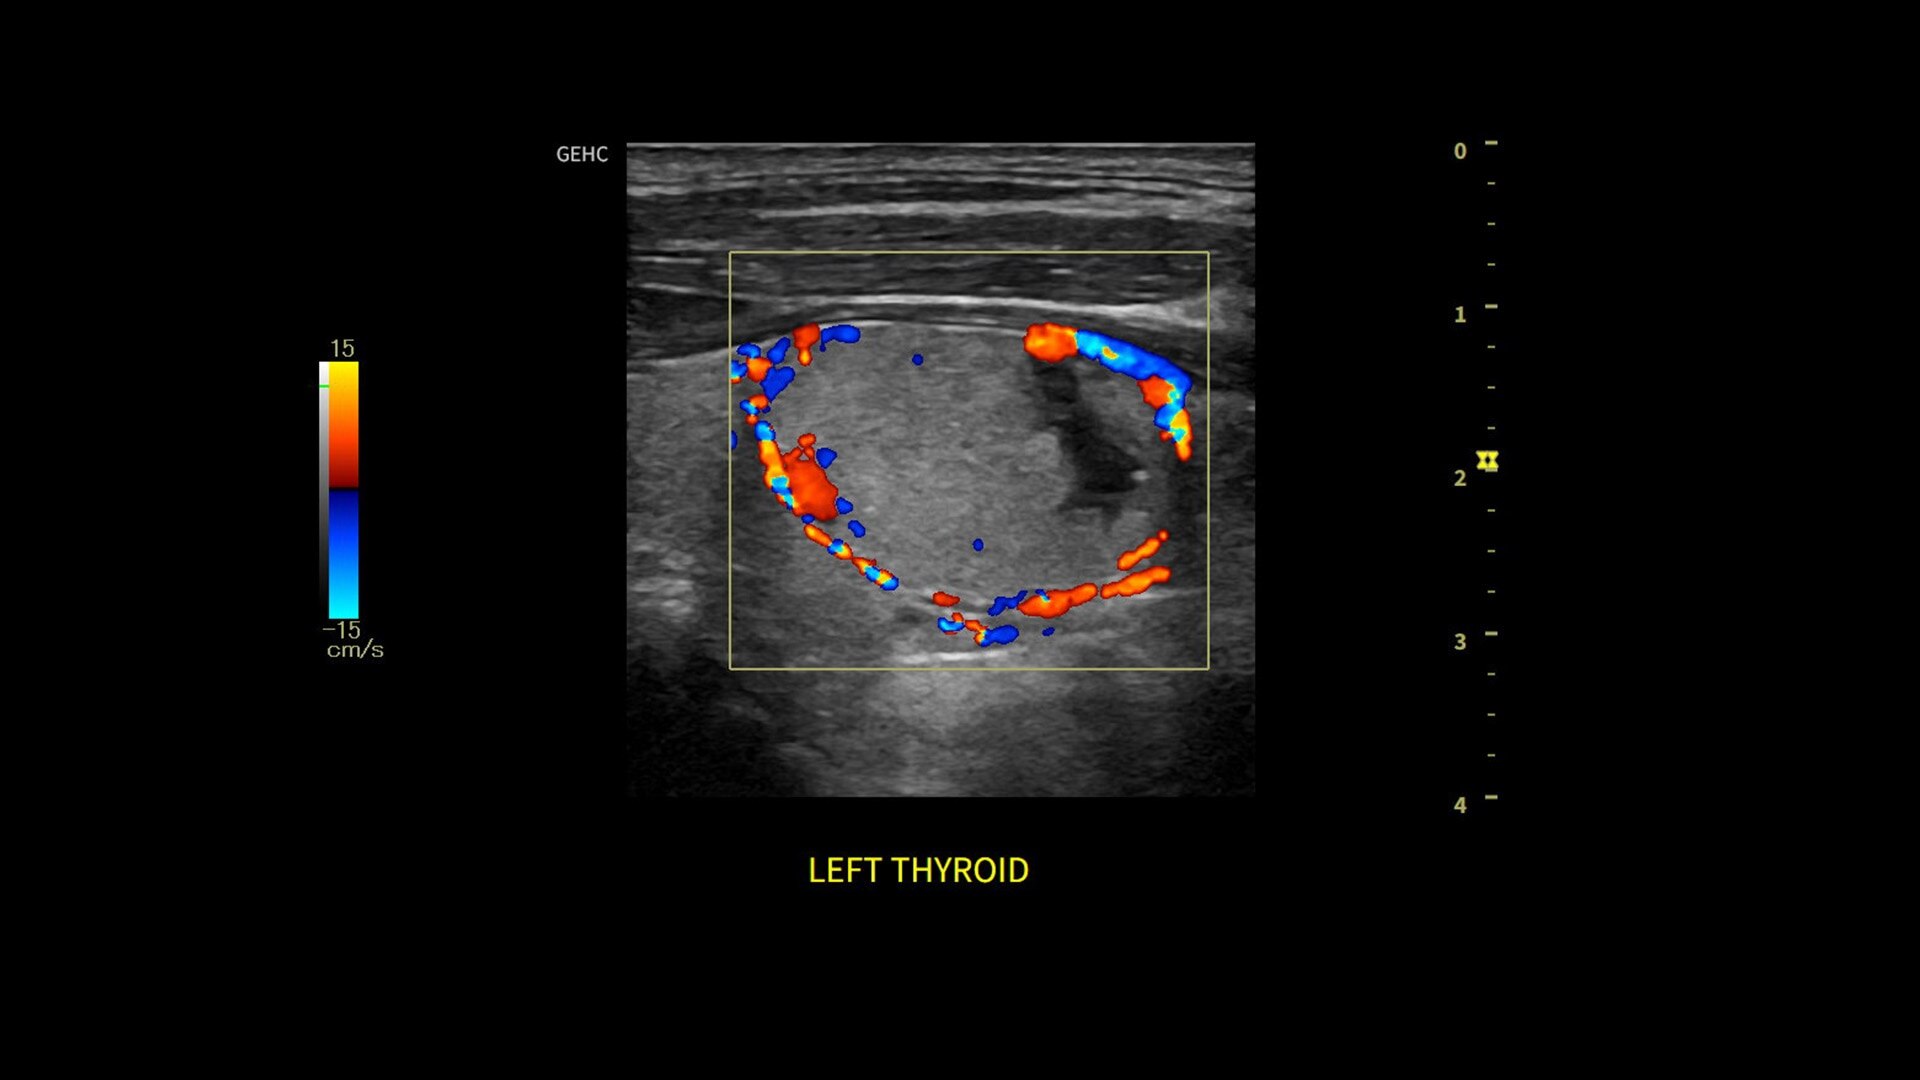

• Optimize images while scanning with Whizz clinical features, easily improve Color Doppler with Whizz Color Flow, and view scans in the image style that suits your preference with Whizz Easy Style

• Assess liver, thyroid and breast nodules with Productivity Packages leveraging LI-RADS,® TI-RADS® and BI-RADS® criteria*